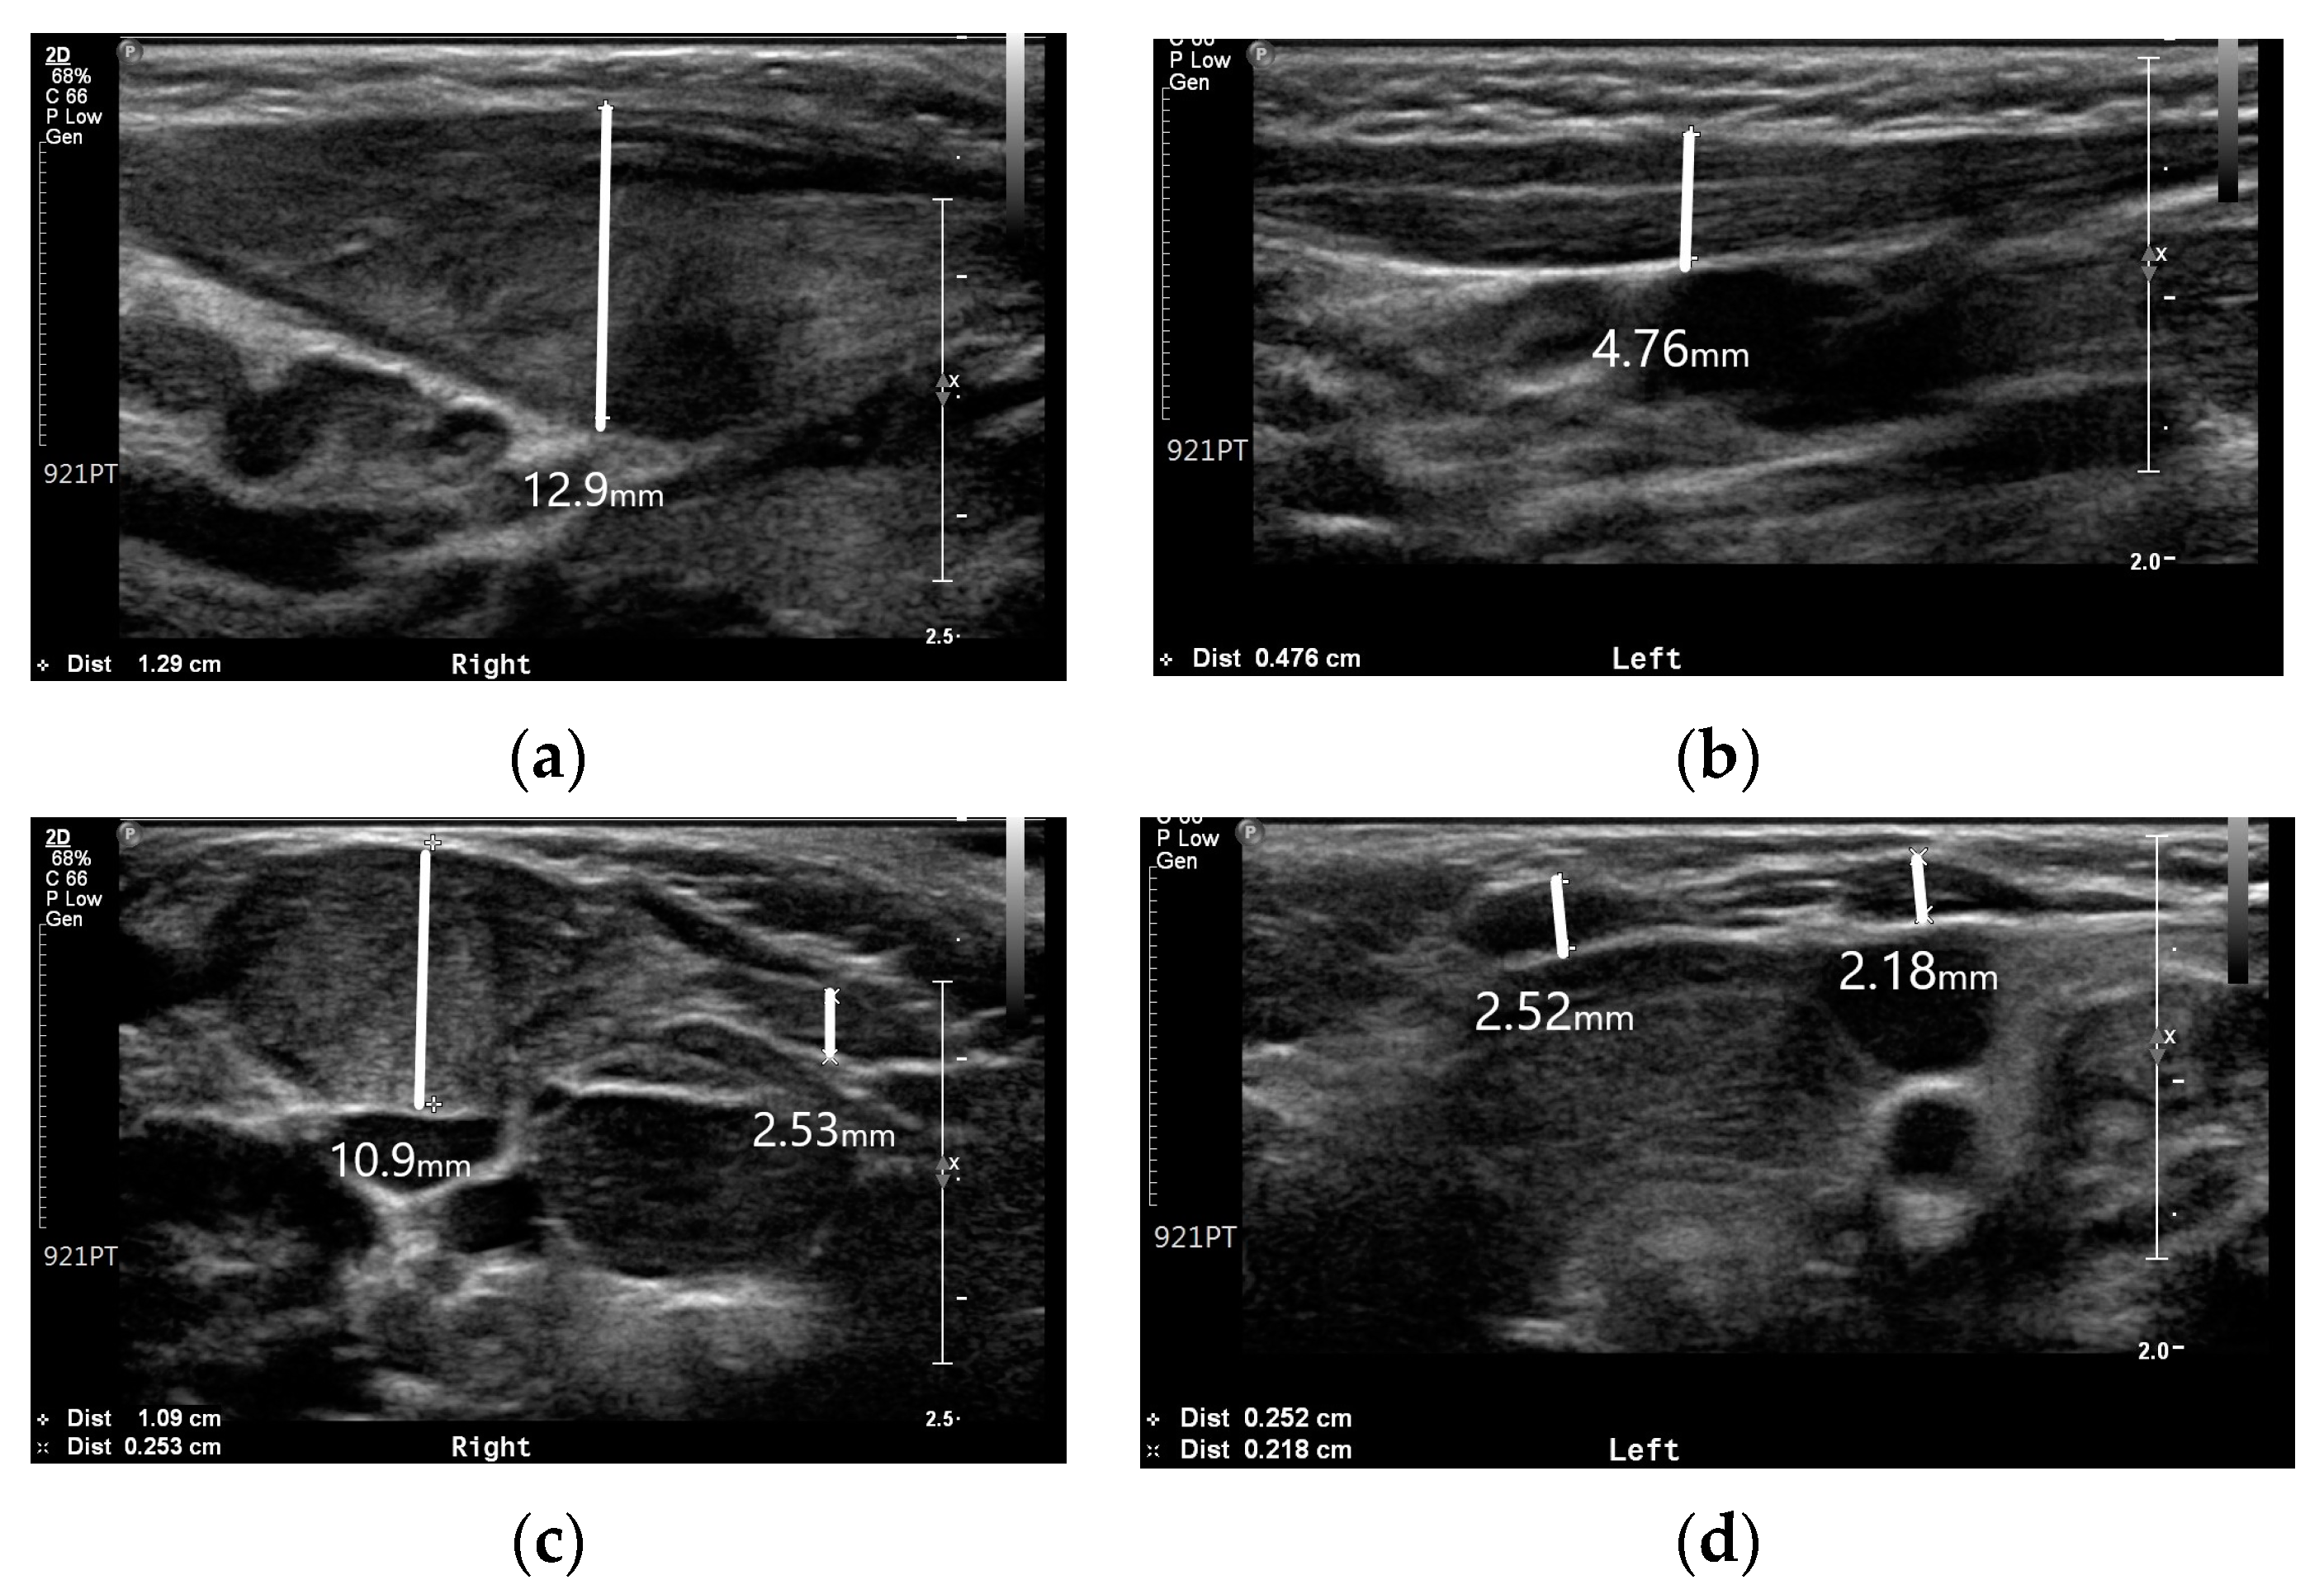

A simple radiographic evaluation was performed to identify any other related complications. To rule out vertebral anomalies, particularly high cervical vertebrae deformations—which could be a cause of congenital torticollis—we examined the cervical spine [9]. The cervical spine simple radiograph was obtained in the anteroposterior view and lateral-extension view (Figure 3). No bony abnormalities or airway obstructions were detected. Whole-spine simple radiography revealed mild right-side thoracolumbar scoliosis (Figure 4). The Cobb angle of the thoracolumbar curve was 12 degrees. Both scanography and pelvic simple radiography revealed no abnormalities in the lower limb and hip regions.

Figure 3. Cervical spine simple radiograph: (a) Anteroposterior view of the cervical spine; (b) Lateral-extension view of the cervical spine.